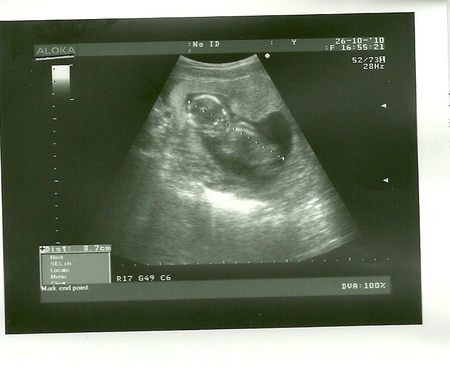

мой карапуз жив)))

После посещения моего Г не могла никак успокоится,тк сердцебиения не было у малыша.не выдержала все таки сходила на узи. Девочки я счастлива

за 2 недельки малыш подрос и стал 8,6см )))) он очень подвижный,я бы даже сказала слишком, с трудом уловили момент чтоб фото сделать)))) а когда услышала сердечко не удержалась расплакалась

. так что теперь я уверенностью могу сказать, тем аппарарам у гиникологов нечего верить. вот такой он сейчас, а может она)))